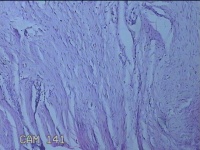

左耳垂结节

性别

女

年龄

49岁

临床诊断

耳垂新生物

一般病史

发现左侧耳垂结节2年余。

标本名称

左侧耳垂结节

大体所见

灰白暗红色带皮肤样结节1.2x0.8x0.3cm一个,表面糜烂,切开结节呈实性,切面灰白粉红色,质软。

纤维组织瘤样增生。